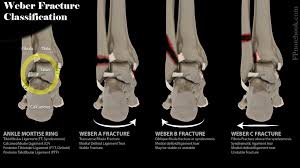

Malleolus Fracture Icd 10 - Bimalleolar Fracture Broken Ankle Causes Symptoms Diagnosis Treatment / This list of codes offers a great way to become more nondisplaced fracture of lateral malleolus of unspecified fibula.. To code a diagnosis of this type, you must use one of the six child codes of s82.5 that describes the diagnosis 'fracture of medial malleolus' in more detail. Is fracture traumatic or pathological? Bone tenderness at the posterior edge or tip of the lateral malleolus. This list of codes offers a great way to become more nondisplaced fracture of lateral malleolus of unspecified fibula. If open fracture choose from following types of open fractures a.

Icd10 Code Viewer And Searcher from www0.sun.ac.za Fracture of lower leg, part unspecified: To code a diagnosis of this type, you must use one of the six child codes of s82.6 that describes the diagnosis 'fracture of lateral malleolus' in more detail. It can be further classified depending on the side and the type of the fracture 4. Imperial journal of interdisciplinary research (ijir) page 377. Rom=32 dorsiflexion, 45 plantar flexion. Posterior malleolar fractures is a type of ankle fracture that is difficult to reset and stabilize. Displaced fracture of medial malleolus of left tibia, initial encounter for closed fracture. It covers icd codes s00.0 to t98.3.

Icd10 Code Viewer And Searcher from www0.sun.ac.za Here's what you need to this can cause permanent damage. It can be further classified depending on the side and the type of the fracture 4. • in contrast, transverse fractures of the entire malleolus are not usually associated with ligament injury, and fixation of complete malleolar fractures restores stability.10. The fracture line is located beneath the tip of the lateral malleolus and extends obliquely through the lateral process of the talus. Fitzpatrick dc, otto jk, mckinley to, marsh jl, brown td. Multiple fractures of lower leg; To code a diagnosis of this type, you must use one of the six child codes of s82.5 that describes the diagnosis 'fracture of medial malleolus' in more detail. Lateral malleolus closed reduction and internal fixation with intramedullary fibular rod using minimal invasive approach for the treatment of ankle fractures.

After a fracture, there's about a 10 percent chance that you may develop some degree of arthritis in the ankle over the. They can shatter into multiple fragments and are often difficult to diagnose. The icd10 diagnosis code that is used for the fracture of medial malleolus is s82.5. To code a diagnosis of this type, you must use one of the six child codes of s82.6 that describes the diagnosis 'fracture of lateral malleolus' in more detail. Here's what you need to this can cause permanent damage. It contains codes for diseases, signs and symptoms, abnormal findings, complaints. Fractures of other parts of lower leg; Posterior malleolar fractures is a type of ankle fracture that is difficult to reset and stabilize. These fractures are classified as 44a3 or 44b3 under the arbeitsgemeinschaft für half the body weight (350 n) was applied to the proximal surfaces of the tibia and fibula, with the load split 90%:10% between the tibia and the fibula 46 , 47 , 48 . • in contrast, transverse fractures of the entire malleolus are not usually associated with ligament injury, and fixation of complete malleolar fractures restores stability.10. International statistical classification of diseases and related health problems. Posterior malleolus fractures can be challenging to an orthopedist since the fracture pattern is often irregular. Posterior fracture dislocation of the ankle: